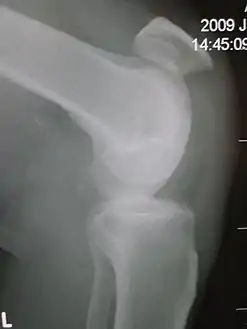

![]() تمزق الأوتار الرضفي يُظهر مسافة ملحوظة بين الحدبة الظنبوبية وأسفل غطاء الركبة. تمزق الأوتار الرضفي يُظهر مسافة ملحوظة بين الحدبة الظنبوبية وأسفل غطاء الركبة. | |

عادة ما يتم تشخيص تمزق وتر الرضفة عن طريق الفحص البدني. العلامات الأكثر شيوعًا هي: الحنان، وفقدان النغمة في الأوتار، وفقدان القدرة على رفع الساق المستقيمة ومراقبة الرضفة عالية الركوب. من الناحية الإشعاعية، يمكن اكتشاف الرضفة ألتا باستخدام طريقة Insall و Salvati عندما تكون الرضفة أقصر من وترها. الدموع الجزئية يمكن تصورها باستخدام التصوير بالرنين المغناطيسي.[11]